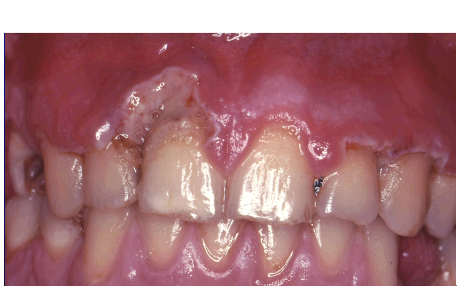

20

Q

what is this

A

necrotising gingivitis